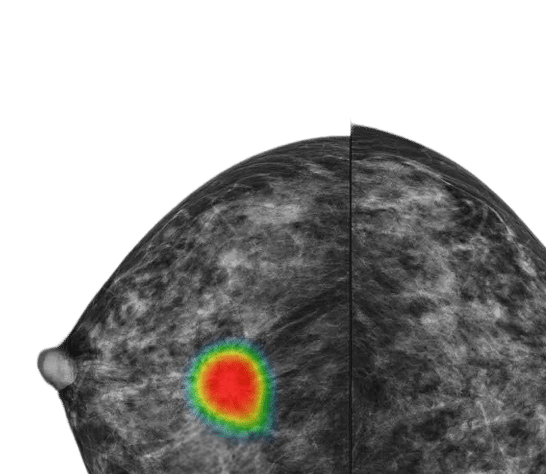

At Lunit, we’re working toward a future where cancer is detected earlier and treated with greater precision, enabling better outcomes for patients.

Our medical AI software transforms complex clinical data into clear, actionable insights, empowering efficient, confident decisions across the care pathway.